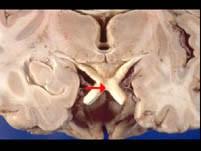

如图箭头所示为视觉系统哪个部位 ( )A、视乳头B、视神经C、视交叉D、视放射E、视束一、单项选择题

问题 如图箭头所示为视觉系统哪个部位 ( )

选项 A、视乳头 B、视神经 C、视交叉 D、视放射 E、视束 一、单项选择题

答案 C